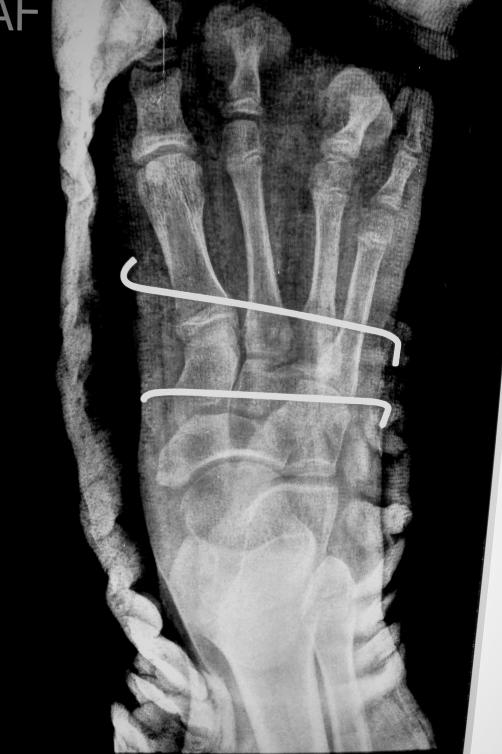

PER OPERATIVE

Removal of 3rd ray

Immediate post-op X-ray